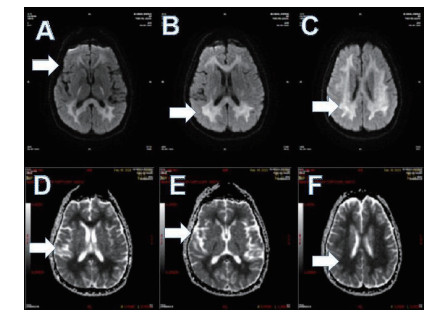

磁共振提示胼胝体局灶病变多为轻症患者(图 3);磁共振提示胼胝体双侧放射冠部散在病变多为中型患者(图 4);磁共振提示胼胝体双侧放射冠区弥漫性病变多为重症患者(图 5,6)。

| 图 4 此图为中型患者,可见胼胝体双侧放射冠部散在病变 |

| 图 5 重型患者,可见胼胝体双侧放射冠区弥漫性病变 |